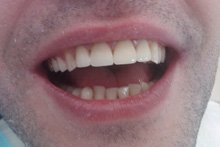

Изменения тканей, которые окружают корни зубов, к сожалению, неизбежны и с возрастом наблюдаются у всех, однако в разном объеме. Так, на развитие пародонтита влияет болезнетворная микрофлора полости рта, которая есть у каждого из нас, но на мы в силах повлиять на ее количество.

Сохранить зубы и пародонт помогает правильная гигиена полости рта дома и в кресле стоматолога, а также своевременное протезирование и имплантация, которые замещают удаленные зубы и равномерно распределяют жевательную нагрузку, не позволяя костной ткани атрофироваться.

Таким образом, по мнению стоматологов, риск возникновения болезней десен на 80% зависит от сознательности самого пациента.